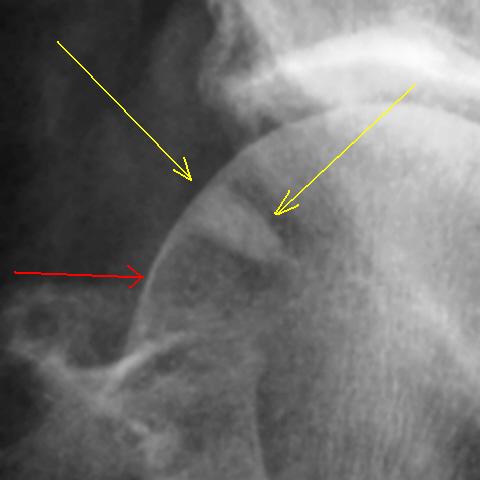

Косой перелом правой тазовой кости без смещения отломков. С момента травмы прошло около 1,5-2,0 месяцев. Пациент направлен "на контрольное исследование".

В верхнем наружном секторе головки бедренной кости визуализируется участок уплотнения вытянутой треугольной формы. Участок помечен желтыми стрелками. Рядом дифференцируется участок просветления - помечен красной стрелкой.

Возник вопрос о субстрате "уплотнения" и "просветления".

УВАЖАЕМЫЕ КОЛЛЕГИ!   Какое Ваше будет мнение по "поводу субстрата".